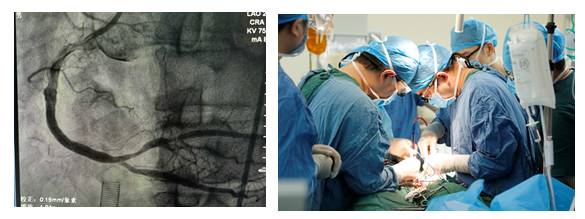

19:30上台

19:37造影:严重的左主干病变!

A. 继续右冠造影?

B. PCI治疗?

C.立即IABP植入?

D. ECMO治疗?

19:46 IABP成功植入

19:53 开始PCI

20:06 球扩后植入1枚支架

20:16 最后结果

◆ECMO 保护下行CAG+PCI干预RCA;